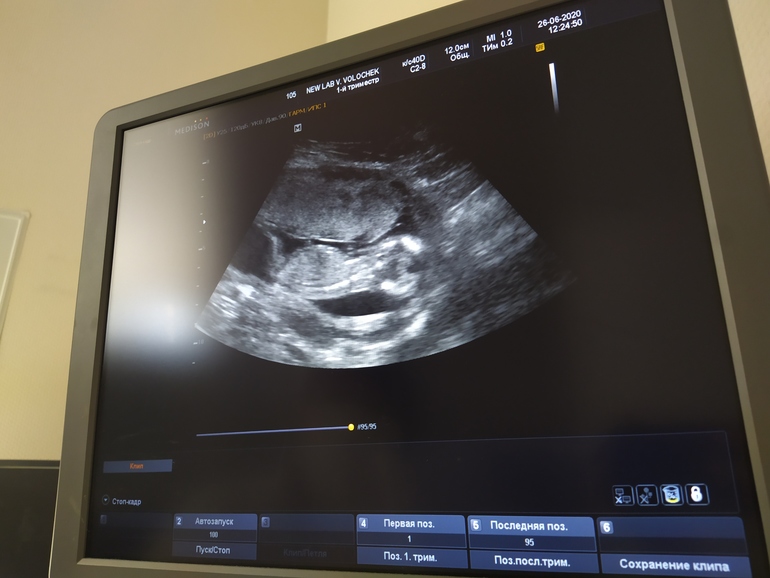

Фотка к сожалению только такая